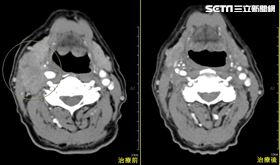

男菸檳酒全包狂瘦7kg 竟是「雙癌鎖喉」

50歲李先生因工作壓力大,每天抽菸、喝酒及嚼檳榔達廿...